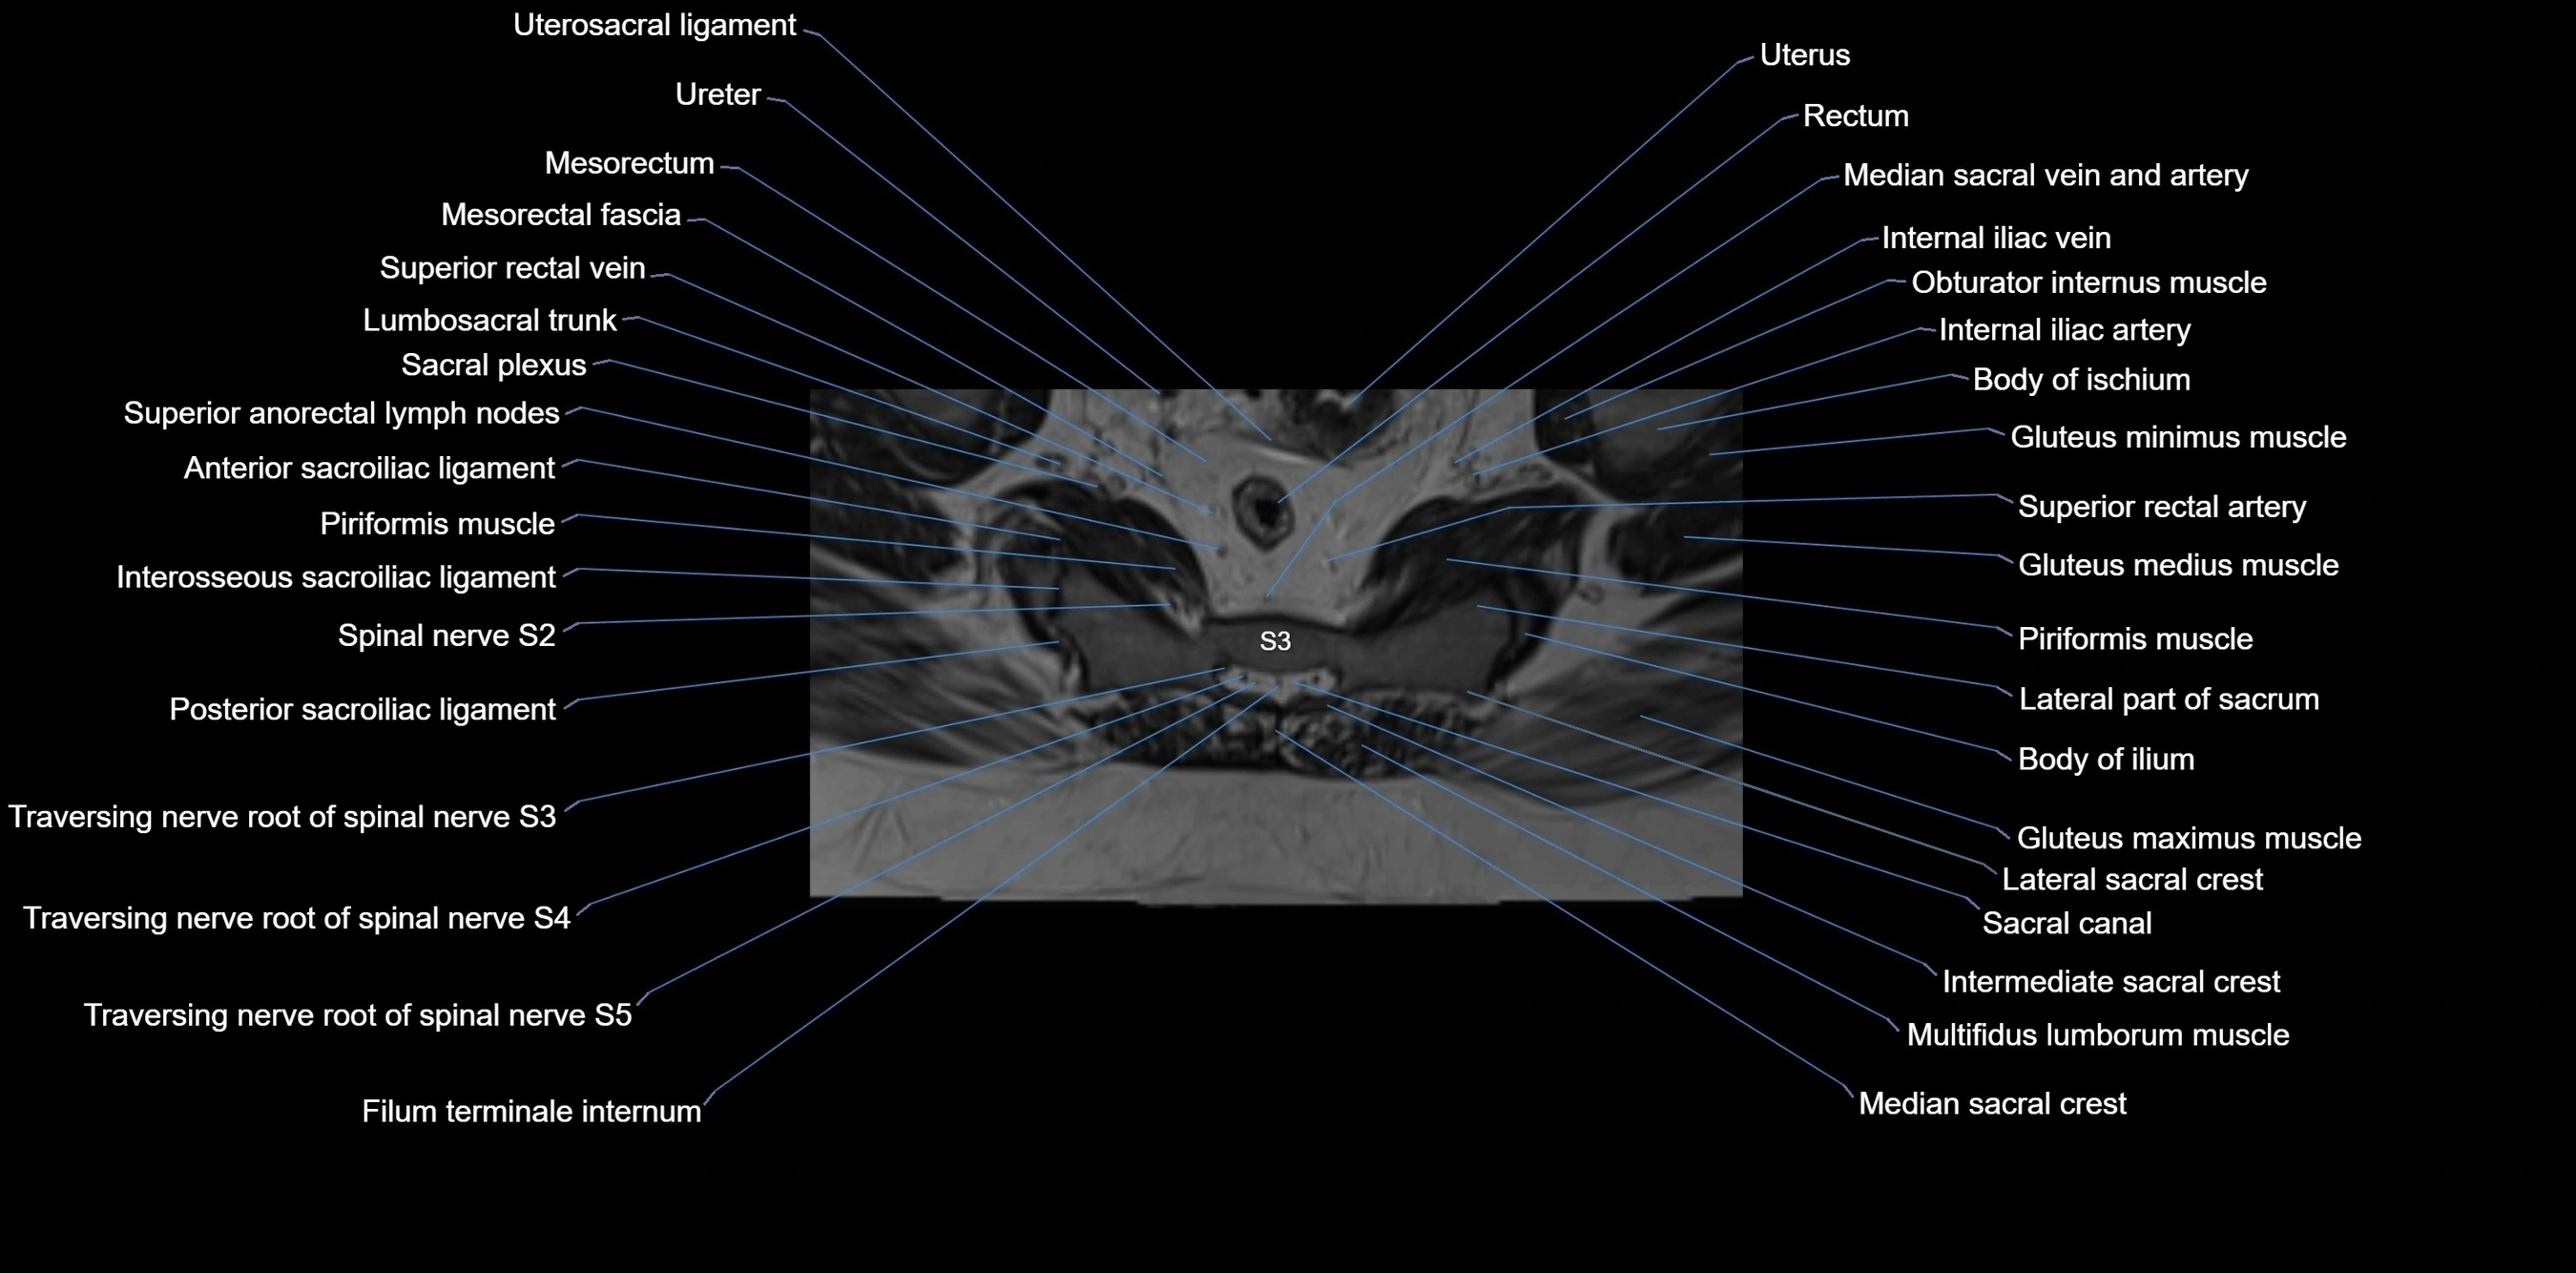

MRI image

image